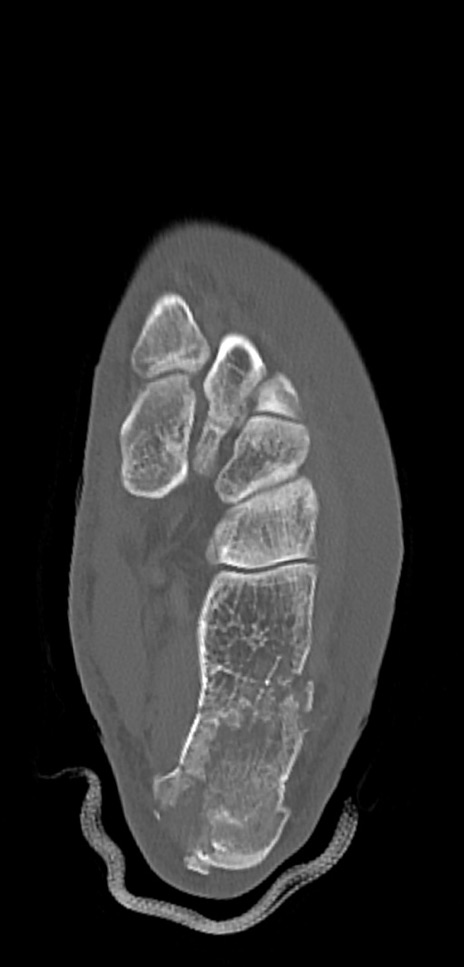

症例37 左足関節CT(横断像)

左足関節CT